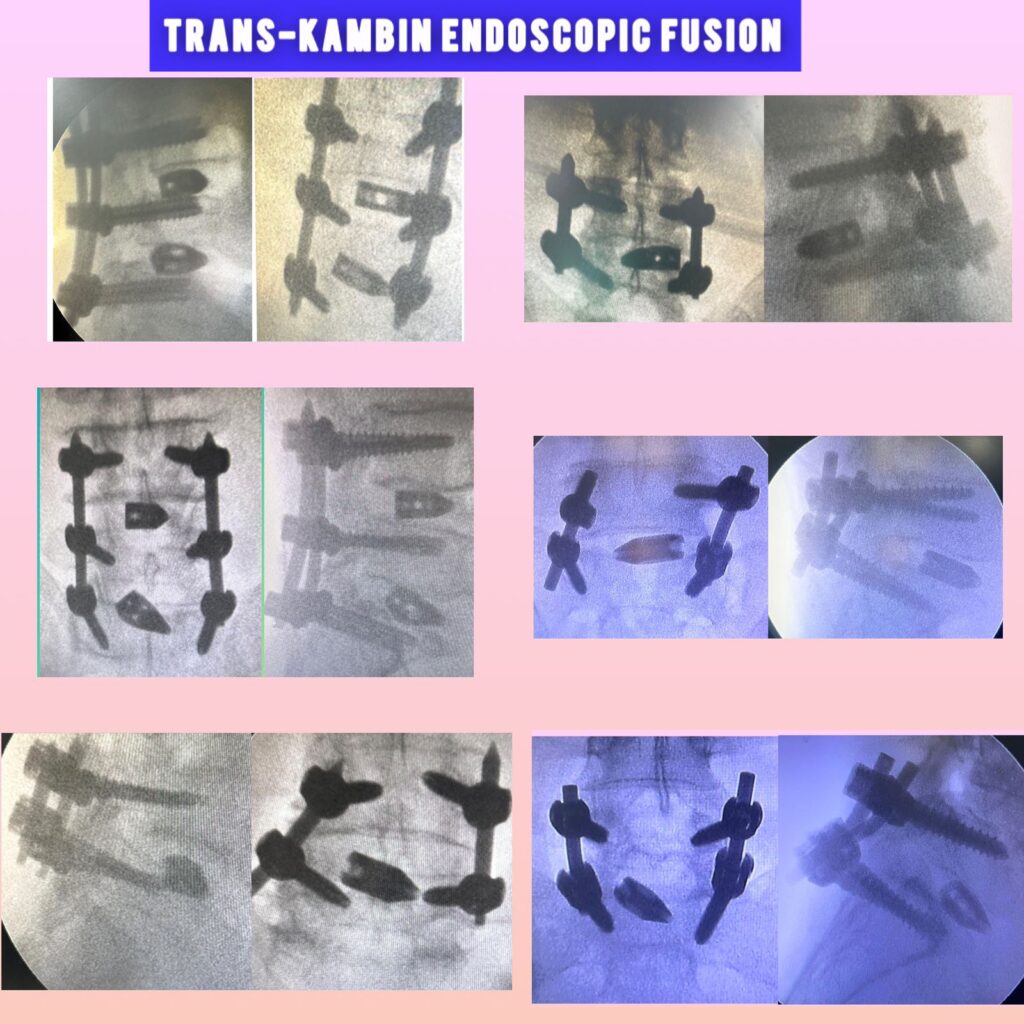

Dr. Ridham Khanderia, MBBS, MS (General Surgery), MCh (Neurosurgery) is a Neuro and Spine Surgeon with over 4 years of clinical experience and more than 2,000 neurosurgical and spine procedures performed. He completed his MBBS from PDU Medical College, MS in General Surgery from MP Shah Medical College, and MCh in Neurosurgery from AIIMS Rishikesh. He also holds a Fellowship in Endoscopic Spine Surgery from Pune.

He specializes in back pain, slip disc, sciatica, and complex spine and brain disorders, with a strong focus on conservative treatment, minimally invasive surgery, and ethical, patient-centered care.